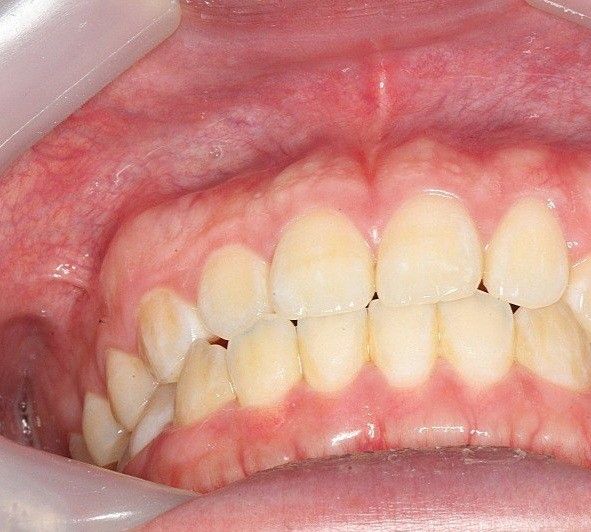

질문1.치아사진보면 잇몸이 볼록 나와있고 잇몸색도 흰색 분홍색 빨간색 섞여있는데 뼈 때문에 볼록한 모양이고 흰색이 섞여있는 건가요?

사진으로 보이는 잇몸은 부착치은이라는 조직으로 잇몸뼈에 단단하게 부착되어 있습니다.

따라서 부착되어 있는 잇몸뼈의 형태가 더 잘 보이게 되는데 치조골이 밖으로 자가 나오거나 한다면 그부위가 상대적으로 흰색으로 보일수 있어요.

정상적인 형태로 보이나 정확한 확인을 위해서 치과에서 진료를 받아 보세요.